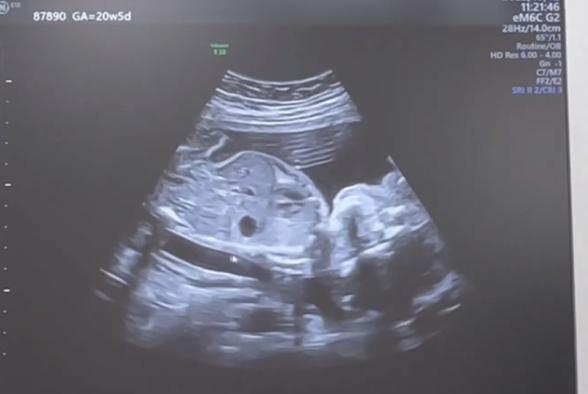

この黒い丸は何でしょうか?

エコーに見られている黒い丸についてですね。

お写真を拝見いたしました。

実際にどのあたりを見ているエコー写真になるのか、よくわからず、お返事が難しいです。

また次の健診の際に、先生へご確認いただけないでしょうか?